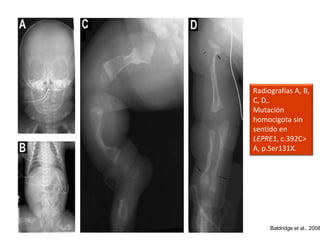

Radiografías A, B,

C, D,.

Mutación

homocigota sin

sentido en

LEPRE1, c.392C>

A, p.Ser131X.

Baldridge et al., 2008